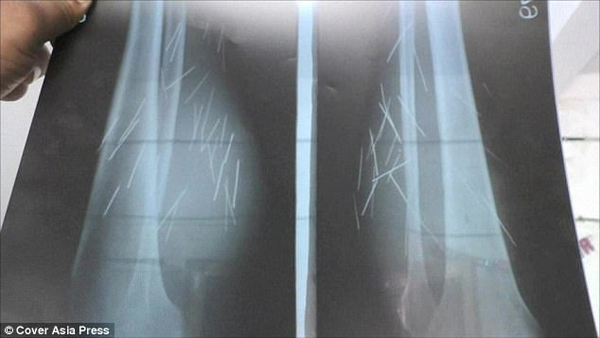

Mãi cho tới ngày 25/10, bác sĩ mới tìm ra được nguyên nhân. Sau khi chụp X quang, họ tá hỏa khi nhìn thấy có 70 vật nhọn bên trong đùi người phụ nữ.

Bác sĩ Naresh Vishal nói: “Cô ấy tới đây trong tình trạng rất đau đớn. Chúng tôi chụp X quang toàn thân cho Devi và phát hiện ra 70 mẩu kim loại trong chân, phần dưới đùi của cô ấy. Chúng tôi chụp toàn thân để xem liệu các mẩu kim loại có xuất hiện ở những bộ phận khác trên cơ thể không. Tuy nhiên, những mẩu kim loại đó chỉ có ở chân“.

Ảnh chụp X quang chân của Devi.